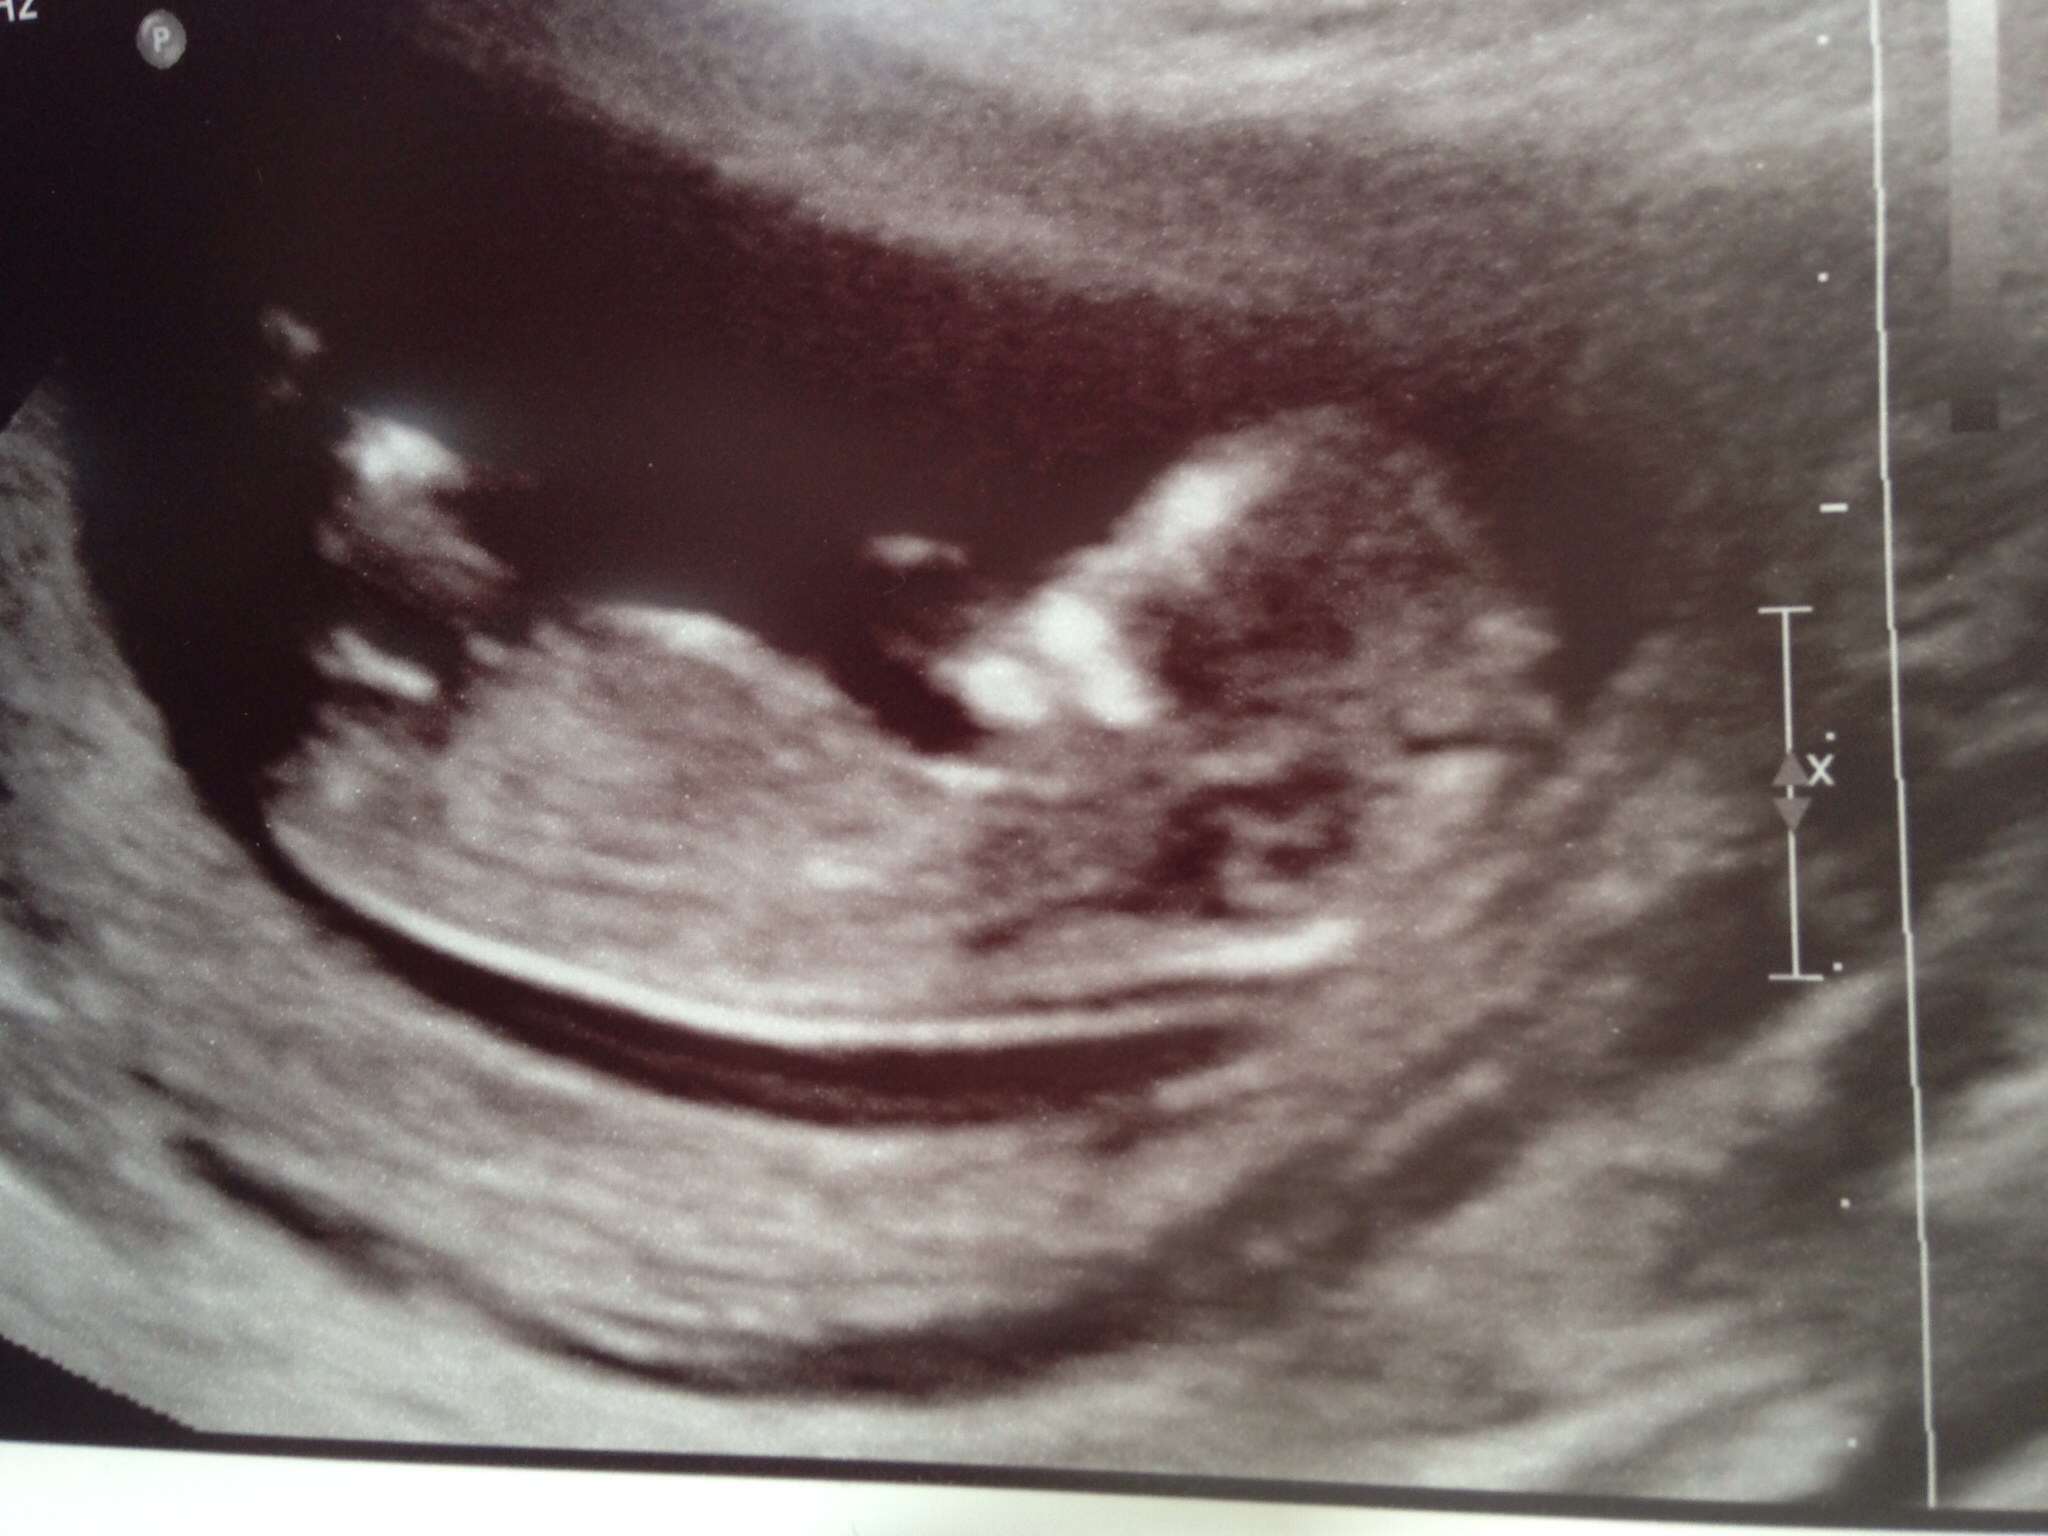

I don't see any clues really but I'm leaning girl!

That looks like a girl nub to me :-)

Still a little early tho.

You are right on the brink of it being too early but I give a girl lean.

Looks girly, for me it is forked